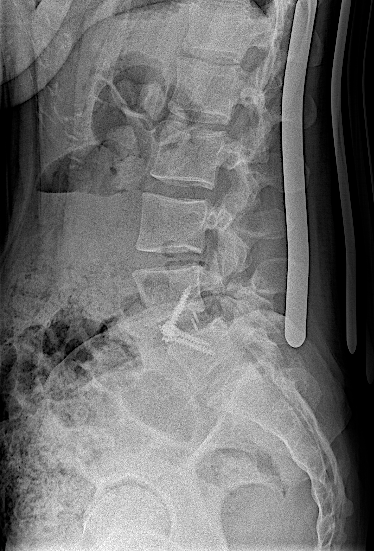

Obsérvese el incremento de la lisis de la pars en las RX dinámicas. La paciente no presentaba clínica radicular significativa por lo que se optó por ALIF L5-L6. El disco L4-L5 presentaba un grado bajo de degeneración.

Tras la intervención, la paciente fue dada de alta sin complicaciones, con corsé y reposo relativo para valorar fijación percutánea en diferido.

Tras retirada de faja, la paciente seguía presentando lumbalgia mecánica. Obsérvese la lisie de la pars.